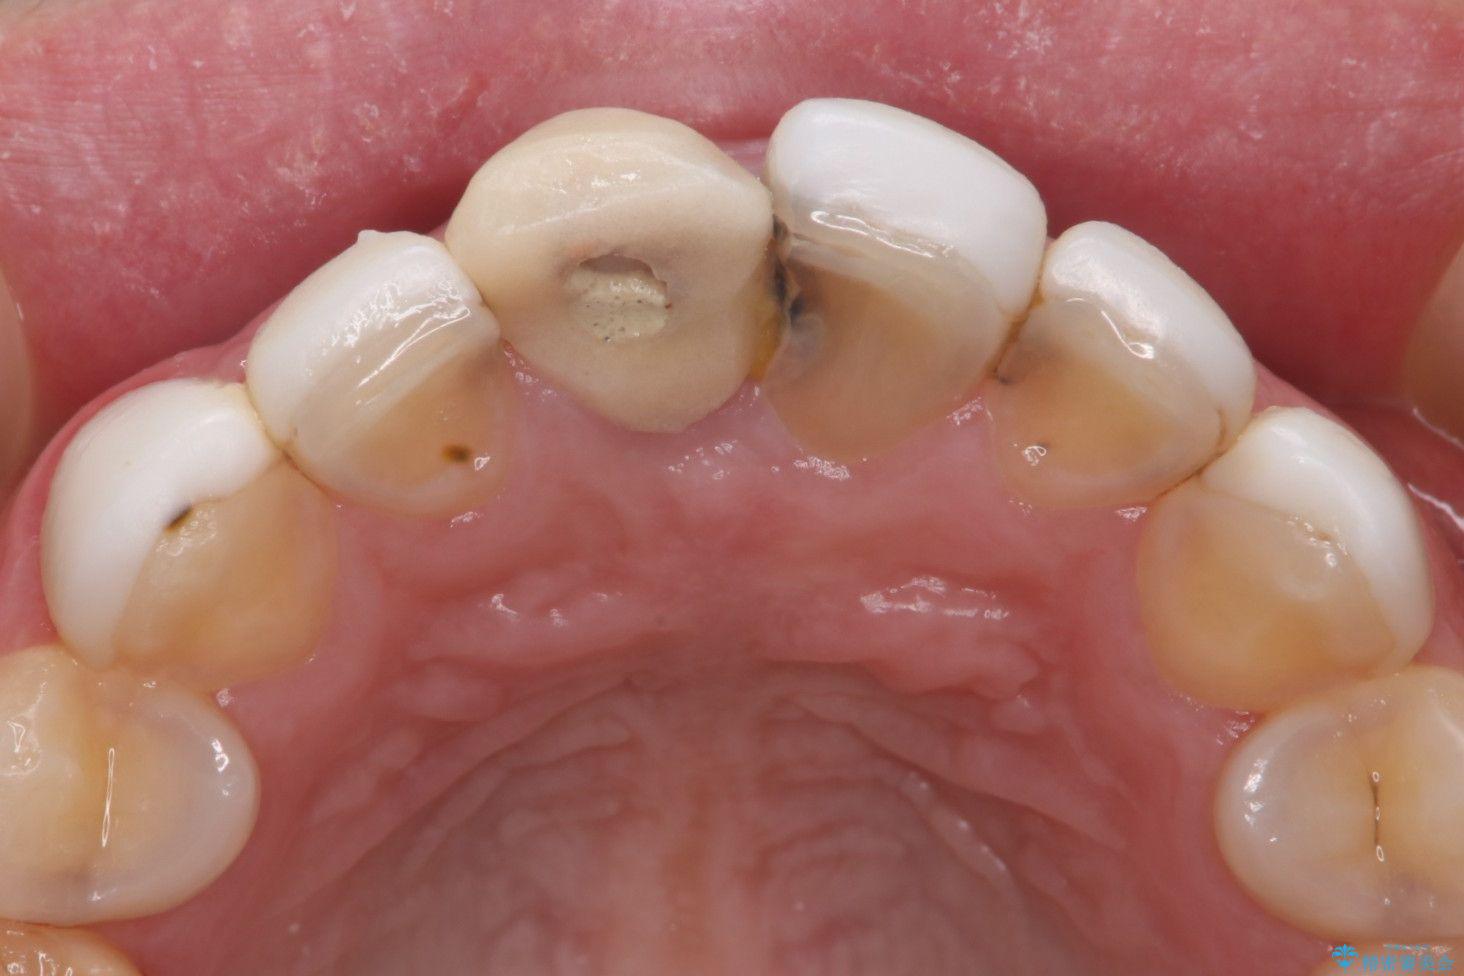

- 他院で治療した前歯の色が気になるということで来院された患者様です。前歯に色の差があり、レントゲンから内部にう蝕も見られたため、審美性に優れ、う蝕になりにくいオールセラミッククラウンで治療いたしました。